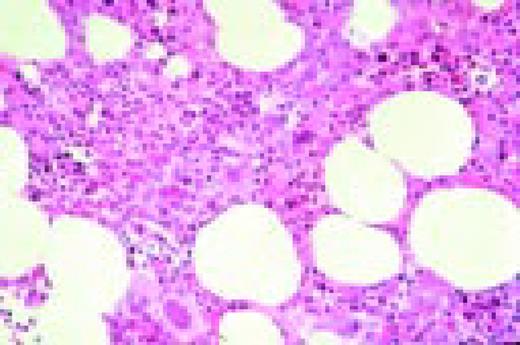

Slide M23

Polycythemia vera, bone marrow. Striking hyperplasia and increased megakaryocytes.FIG76